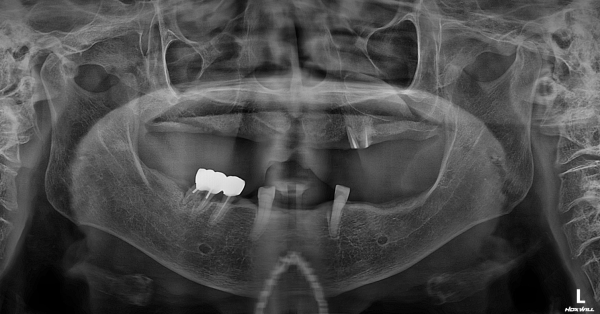

정밀 진단 – 틀니가 아닌 ‘뼈’의 문제

3D CT 정밀 촬영 결과,

아래턱 치조골이 심하게 흡수되어

틀니가 붙잡을 기반 자체가 거의 사라진 상태였습니다.

단순 틀니 재제작으로는

근본적인 해결이 어려운 상황.

또한

고혈압

고지혈증

80대 후반 고령

전신질환을 고려해

‘안전 최우선’ 맞춤 치료 계획을 수립했습니다.